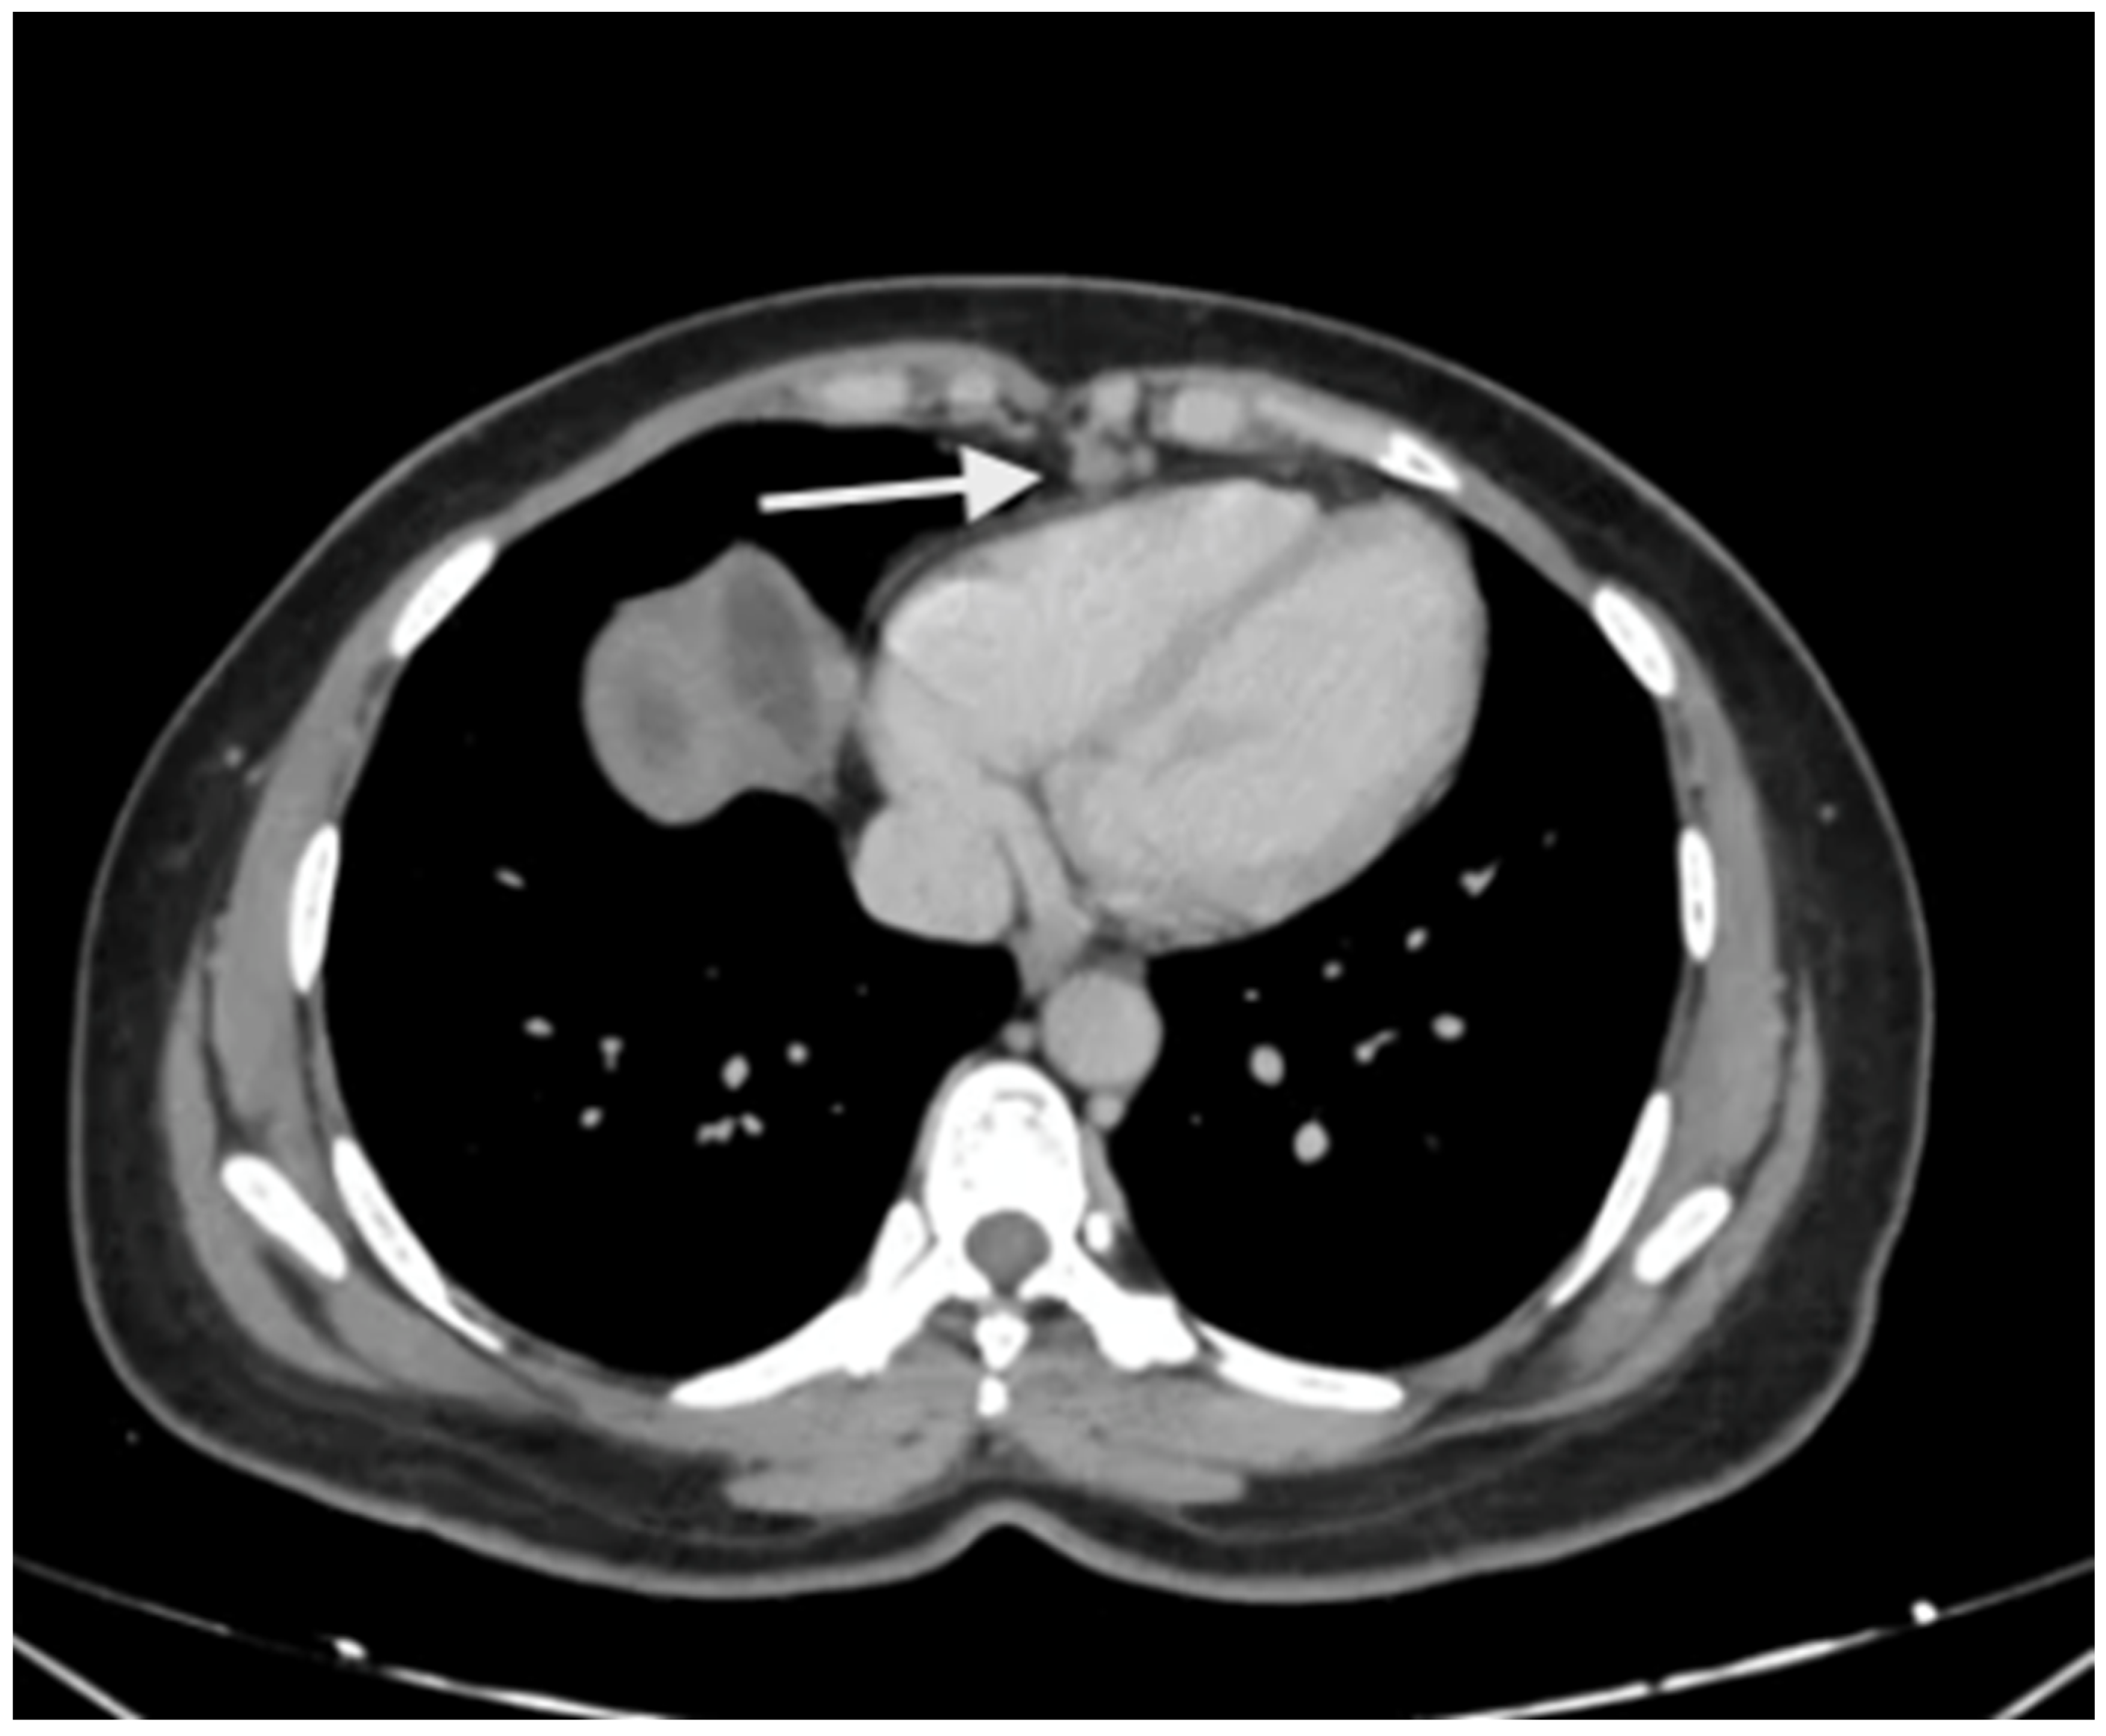

5. Preoperative Imaging